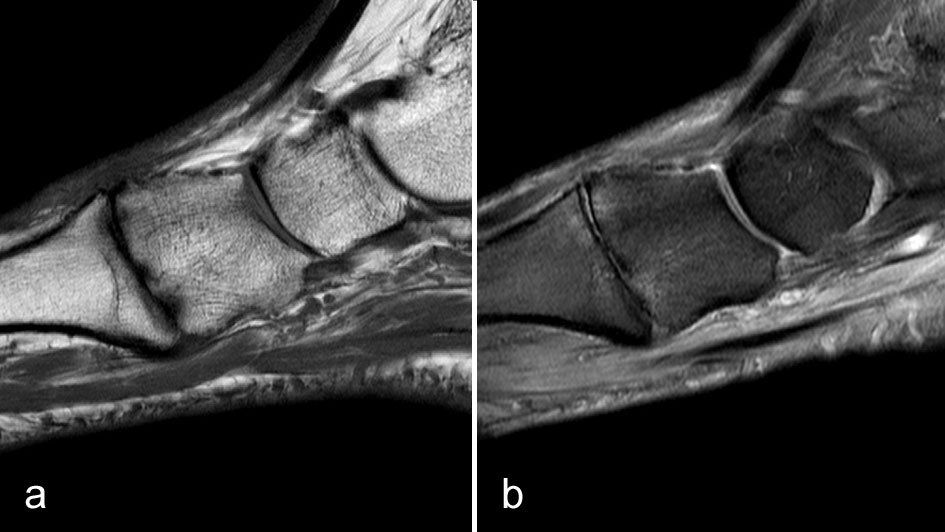

Degenerative Veränderungen im Bereich der Fußwurzel und tarsometatarsal sind wiederum häufig schmerzhaft. Es zeigen sich die klassischen morphologischen Veränderungen der Gelenkdegeneration (Gelenkspaltverschmälerungen, Osteophyten, Zystenbildungen, subchondrale Knochenmarkveränderungen) (Abb. 16) und häufig Zeichen der entzündlichen Aktivierung (Erguss, Synovialitis, Kapselschwellung).

Die Diagnose ist meist schon klinisch und radiographisch zu stellen. Eine relativ häufige Differenzialdiagnose, die klinisch wie eine mediale tarsometatarsale Degeneration imponieren kann, ist die Tendinopathie der Tibialis anterior Sehne (Abb. 17).